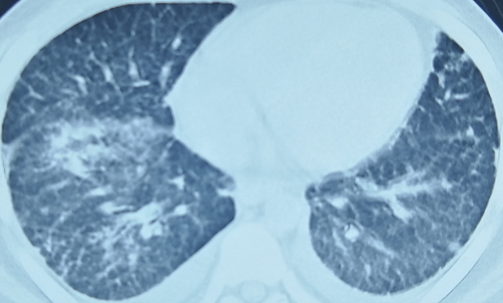

影像学检查

两肺可见散在小结节状、斑片状密度增高影及模糊影、少许条索影

影像学诊断:

1、两肺散在病灶,考虑炎症,嗜酸性粒细胞性肺炎?

2、双侧筛窦、左侧额窦及右侧上颌窦炎症。